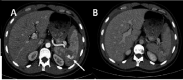

Blunt trauma is still the leading mechanism of trauma found in patients admitted to trauma centres worldwide. In these patients, the gastric injury is a very rare lesion, occurring in less than 2% of all blunt traumas. Besides the low incidence, gastric rupture mortality is high, which makes the diagnosis an essential step. Thus, this study aims to report two blunt gastric injuries, with different clinical features, prompting the discussion about the main features of clinical suspicion and diagnosis, besides the main therapeutic approaches. Therefore, this study can alert the medical community to the quick diagnosis and assertive therapy, saving patients of unwelcome endpoints.